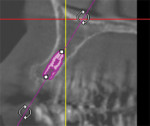

Planning and execution are key elements for successful dental treatment. Specific to implant cases, planning incorporates a CBCT for anatomical analysis and implant selection, a surgical guide for implant placement, and HIPAA-compliant communication for interdisciplinary collaboration. Execution involves choosing the right materials. Prosthetic materials are highly relevant to the longevity of a restoration. For an implant case, this includes impression materials to ensure an appropriate transfer of the clinical situation. For the case detailed here, Aquasil® Ultra+ Smart Wetting Impression Material (Dentsply Sirona Restorative, aquasilultraplus.com) was selected because of its simple delivery system, its wash material with excellent hydrophilicity and tear strength, and a heavy-body composition that provides compression and border molding. These features allow for the necessary physical and special detail reproduction and help prevent trapping voids or the loss of material in the mouth upon impression removal. The quick set of the material, together with a pleasant taste and thixotropy characteristic, enables a positive patient experience. Also, Aquasil Ultra+ is versatile across both implants and natural tooth preparations.